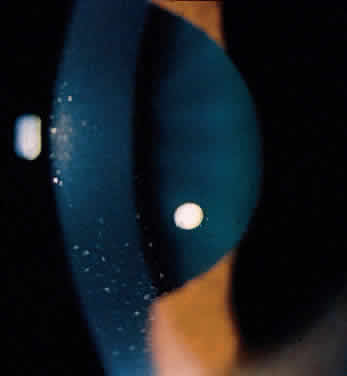

The conjunctivitis is usually described as mucopurulent and may be sterile. It may be accompanied by an iridocyclitis, episcleritis, or scleritis. Punctate and subepithelial corneal involvement has been reported. The iridocyclitis may be the presenting ocular manifestation. Recurrences are usually associated with an acute iridocyclitis, which is of rapid onset with conjunctival and episcleral edema and injection. The corneal endothelium has cellular debris and poorly defined, small-sized to medium-sized keratic precipitates.30 Heavy flare and cells and a very early tendency toward formation of posterior synechiae is characteristic, more so than in most other forms of acute iridocyclitis (Figs. 1, 2, and 3). Even the most aggressive pupil dilation management is sometimes inadequate for preventing synechiae. A peripheral iridectomy may be necessary to prevent iris bombé and angle closure if the synechiae cannot be broken enough to establish an opening for aqueous through the pupil (Fig. 4). The heavy flare is sometimes so plasmoid that cells are immobile and a fibrinlike clot may be seen in the pupil opening as the inflammation resolves. Cells and inflammatory debris may be seen in the vitreous, and blurring of the disc margins and macular edema may occur with severe or prolonged episodes. Lens clouding and posterior subcapsular cataracts occur with prolonged or repeated episodes. Hypotony can occur after a severe or prolonged course and may persist after resolution. Occasionally, secondary glaucoma may occur, owing to the anterior chamber reaction, in which case it will resolve as the inflammation resolves. With repeated recurrences, damage to the trabecular meshwork may occur, and prolonged recalcitrant glaucoma may result that may be poorly responsive to any medical or surgical management. This can be a serious factor in permanent visual loss with this type of iridocyclitis.15,16,30,31

Fig. 1. Early onset complete posterior synechiae in iridocyclitis with Reiter's disease.

Fig. 2. Partial dilation of pupil in Figure 1.

Fig. 3. Completed dilation of pupil in Figure 1 with pigment on anterior surface of the lens.